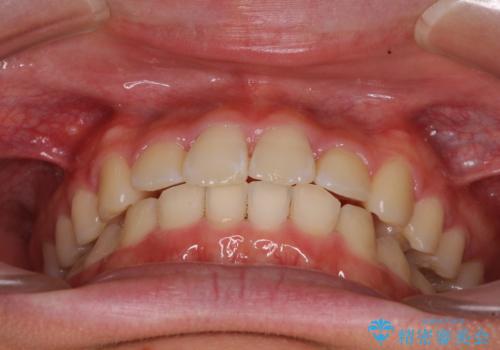

深い咬み合わせとデコボコ ワイヤー矯正で短期治療

インビザラインでの治療も可能でしたが、深い咬み合わせと奥歯の咬み合わせを改善するにあたり、ワイヤー矯正の方が治療期間を短縮できると判断し、ワイヤー矯正をお勧めしました。

結果として、1年かからずに奥歯の咬み合わせを改善することができました。